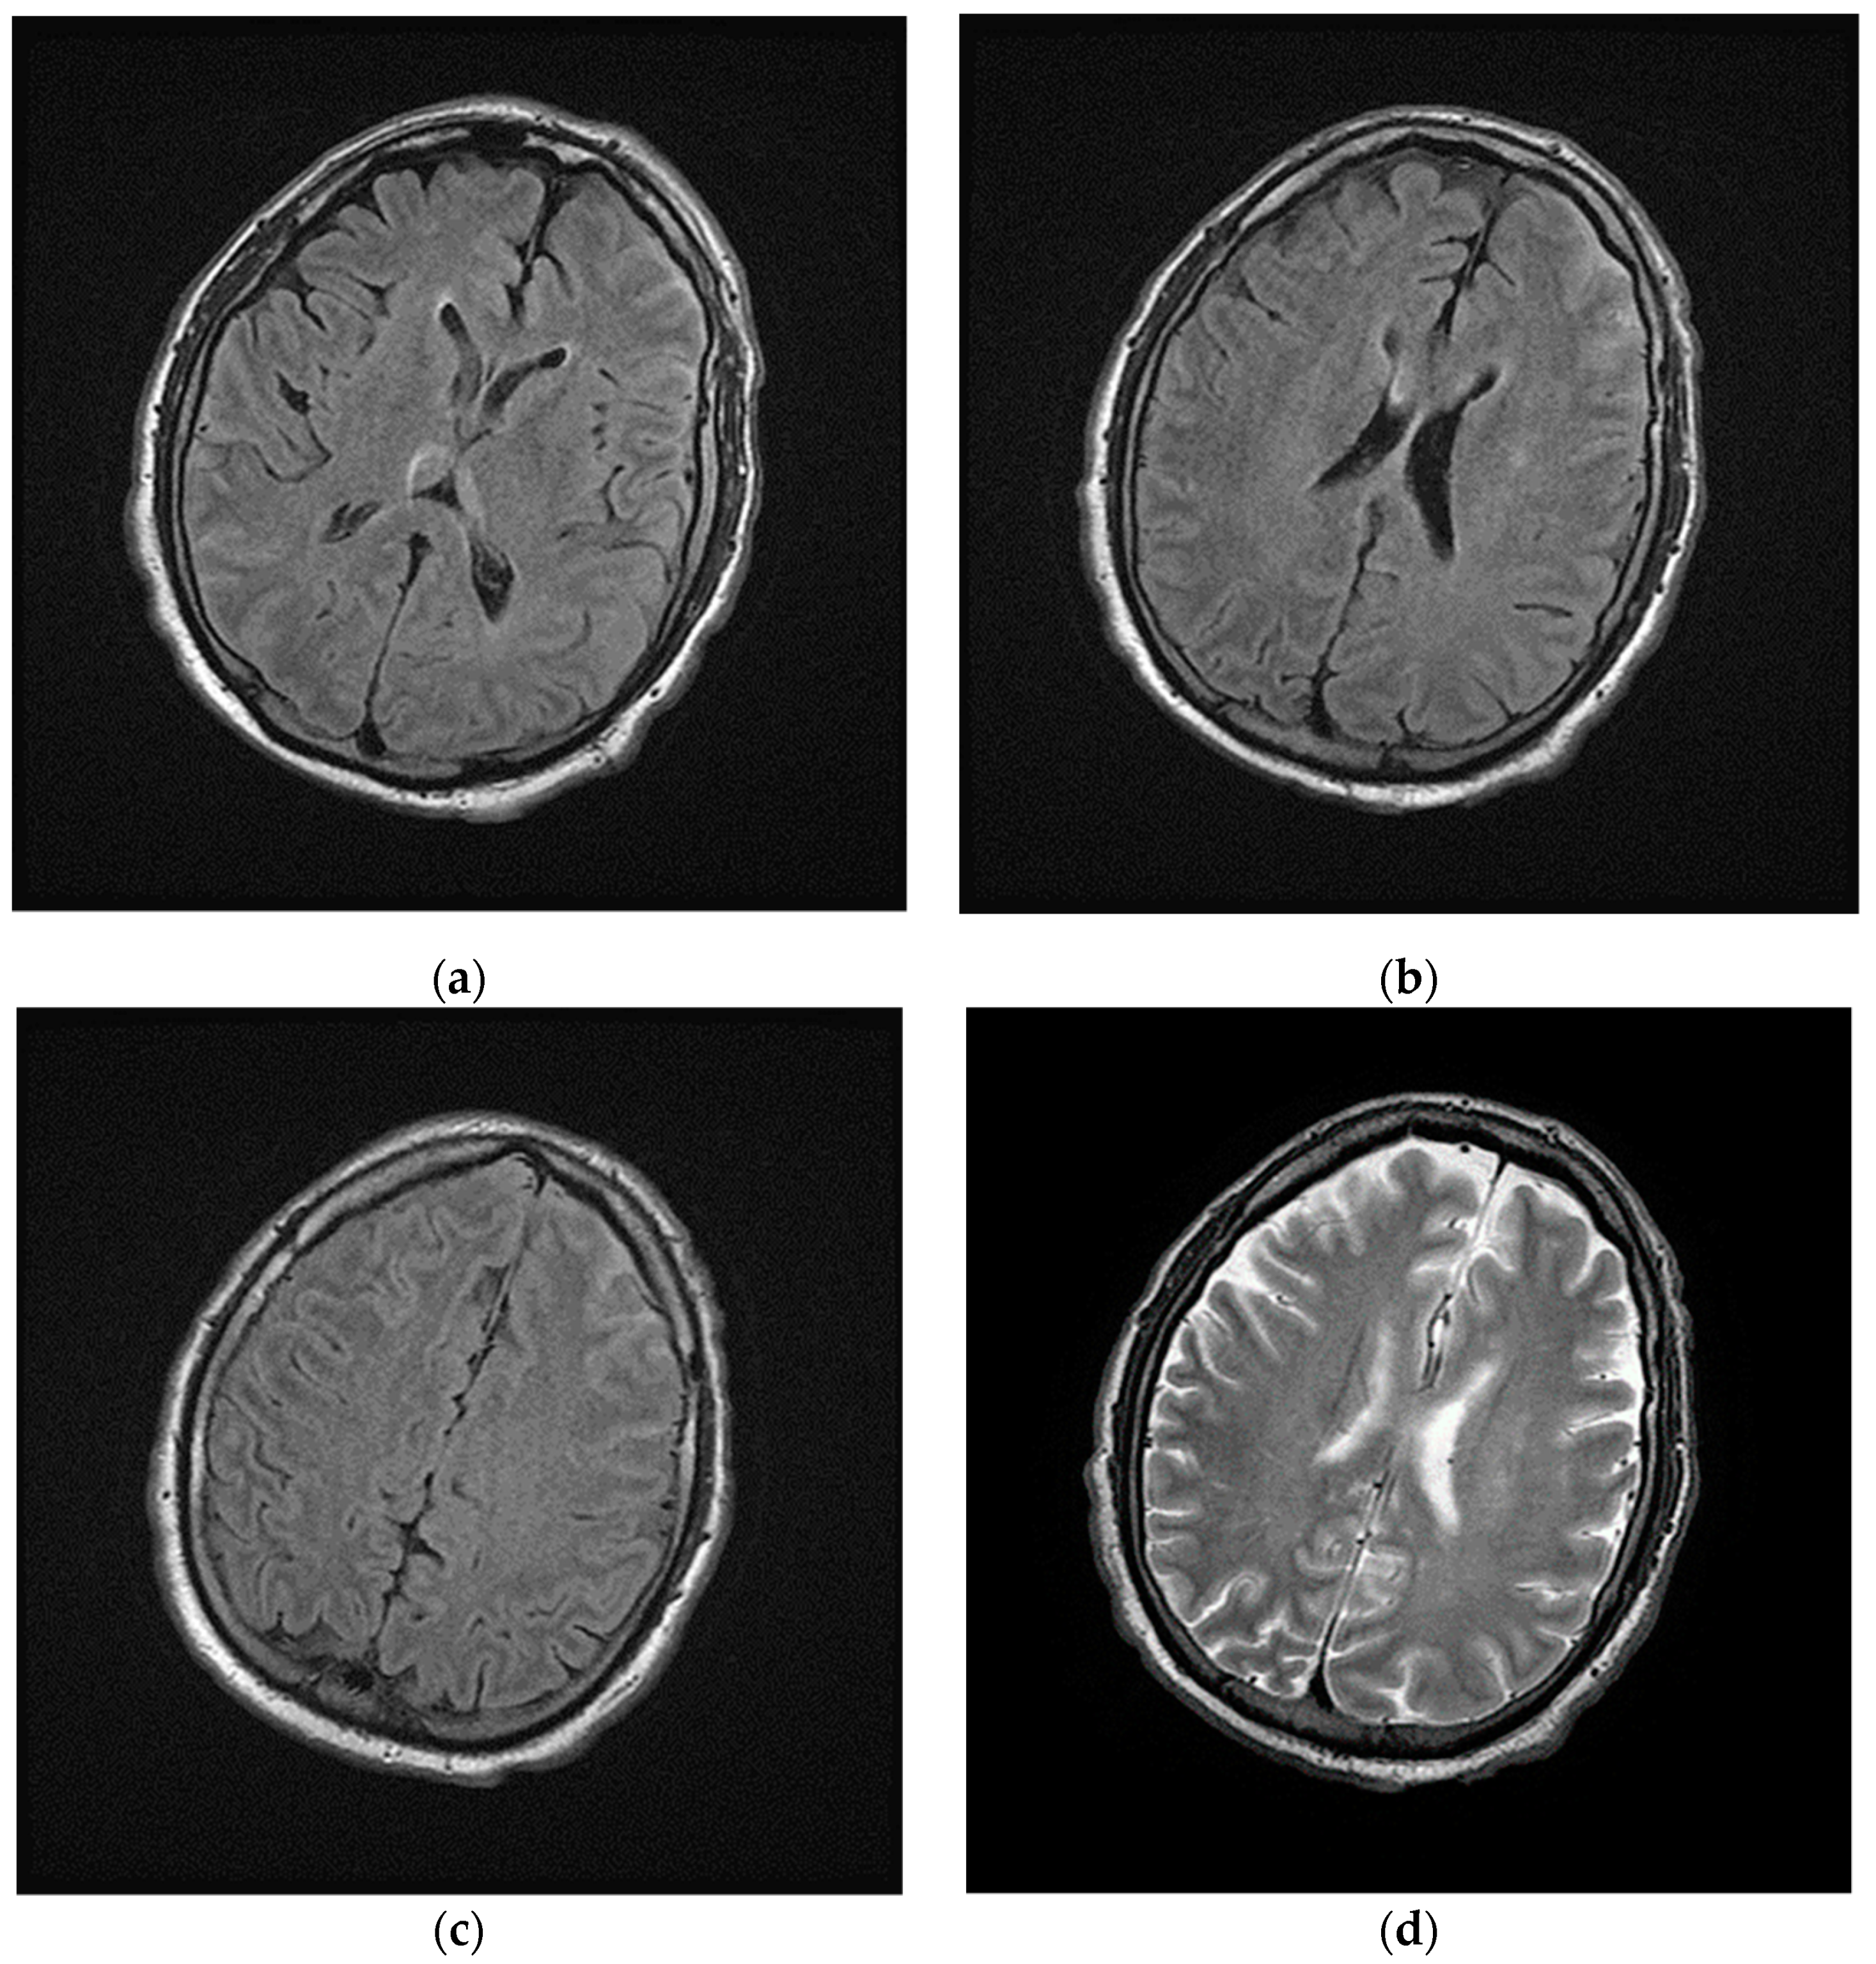

2.2. Post Hospital Phase